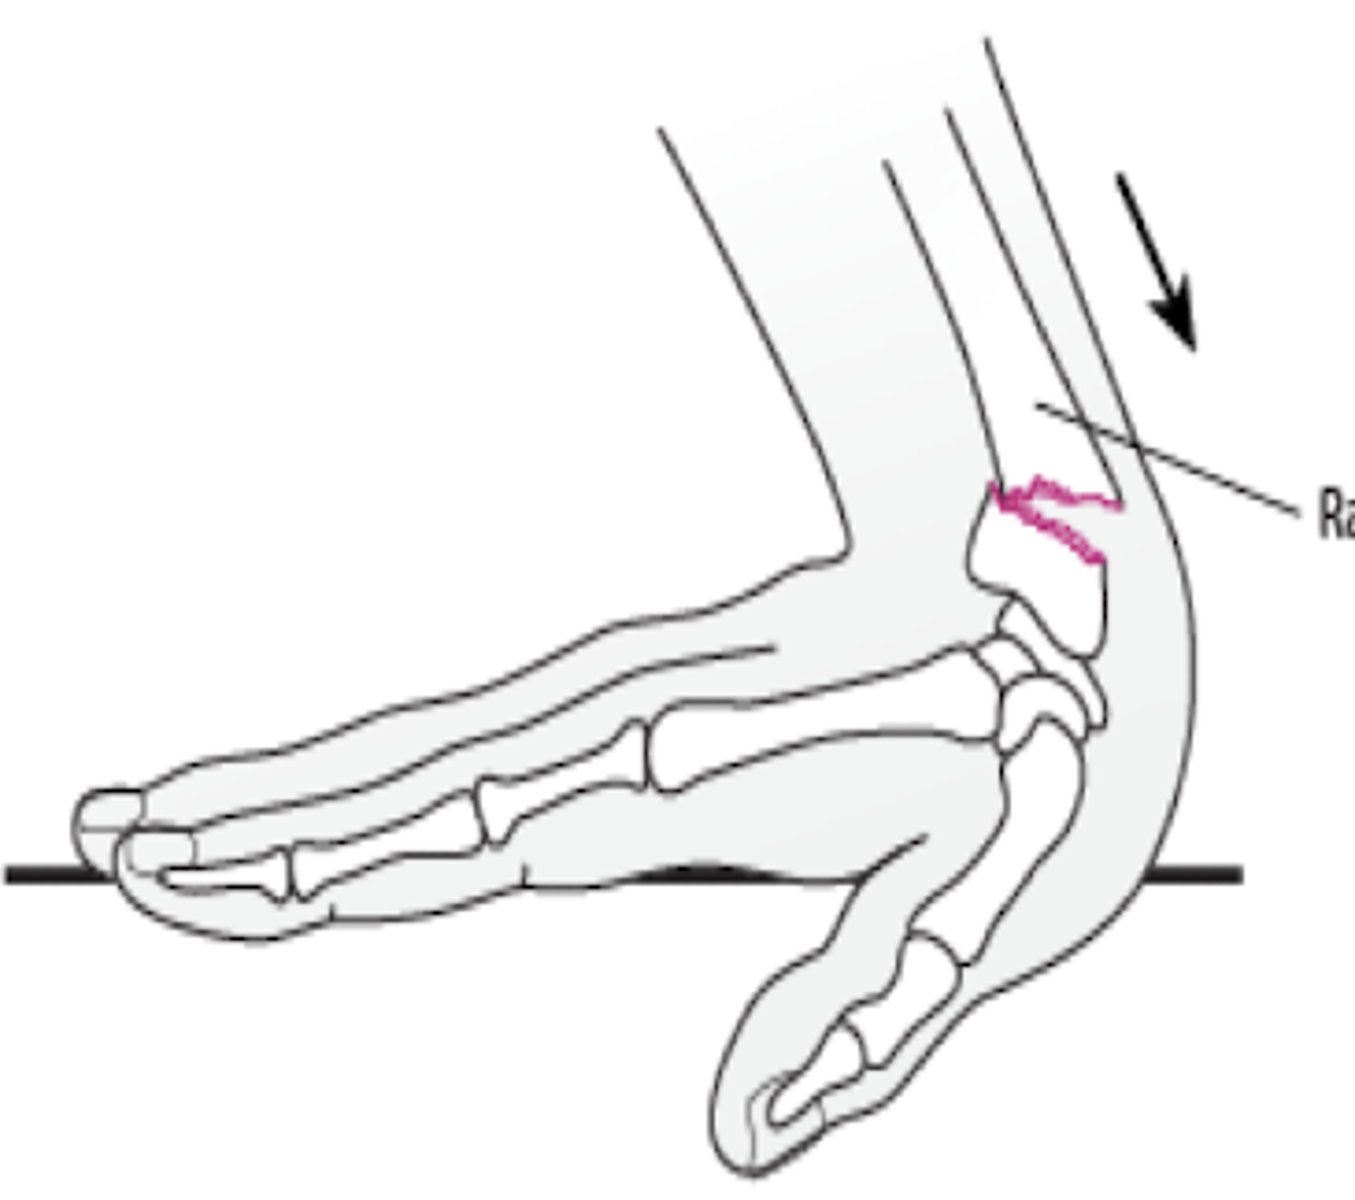

radial and ulnar fractures mechanism of injury

Colles fracture; dinner fork

distal 2 cm transverse fracture of radius with dorsal displacement and will have this type of_____ deformity

Colles fracture

dorsal displacement of radius (distal 2 cm transverse fracture)

Smith fracture

volar displacement of radius (distal 2 cm transverse fracture)

volar displacement of radius